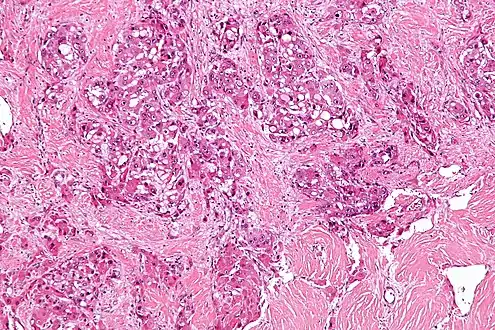

| Micrograph of fibrolamellar hepatocarcinoma showing the characteristic laminated fibrosis between the tumor cells with a low NC ratio. H&E stain. | |

The histopathology of FLC is characterized by laminated fibrous layers, interspersed between the tumor cells. Cytologically, the tumor cells have a low nuclear to cytoplasmic ratio with abundant eosinophilic cytoplasm.[1] Tumors are non-encapsulated, but well circumscribed, when compared to conventional HCC (which typically has an invasive border).